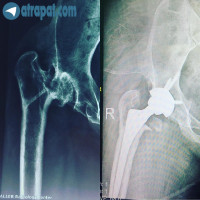

دو ماه بعد از تعويض مفصل هر دو زانوبيمار خانم ٦٥ ساله ٦ ماه پس از تعويض مفصل هر دو زانوآقاي ٤٦ ساله با بيماري در فتگي مادرزادي هيپ وكوتاهي اندام تحتاني راست مراجعه كرده ،كه پس از تشخيص تحت عمل جراحي توتال هيپ قرار گرفته است .

عكس قبل و بعد از عمل جراحيبيمار خانم ٦٠ ساله

دو هفته پس از عمل جراحي تعويض مفصل زانو (پروتز زانو)بيمار خانم ٦٥ ساله ،حدود يك ماه بعد از عمل تعويض مفصل زانواقاي ٧٠ ساله با پروتروژن هيپ راست تحت عمل جراحي توتال هيپ و گرفت استابولوم قرار گرفتهبيمار خانم ٦٧ ساله